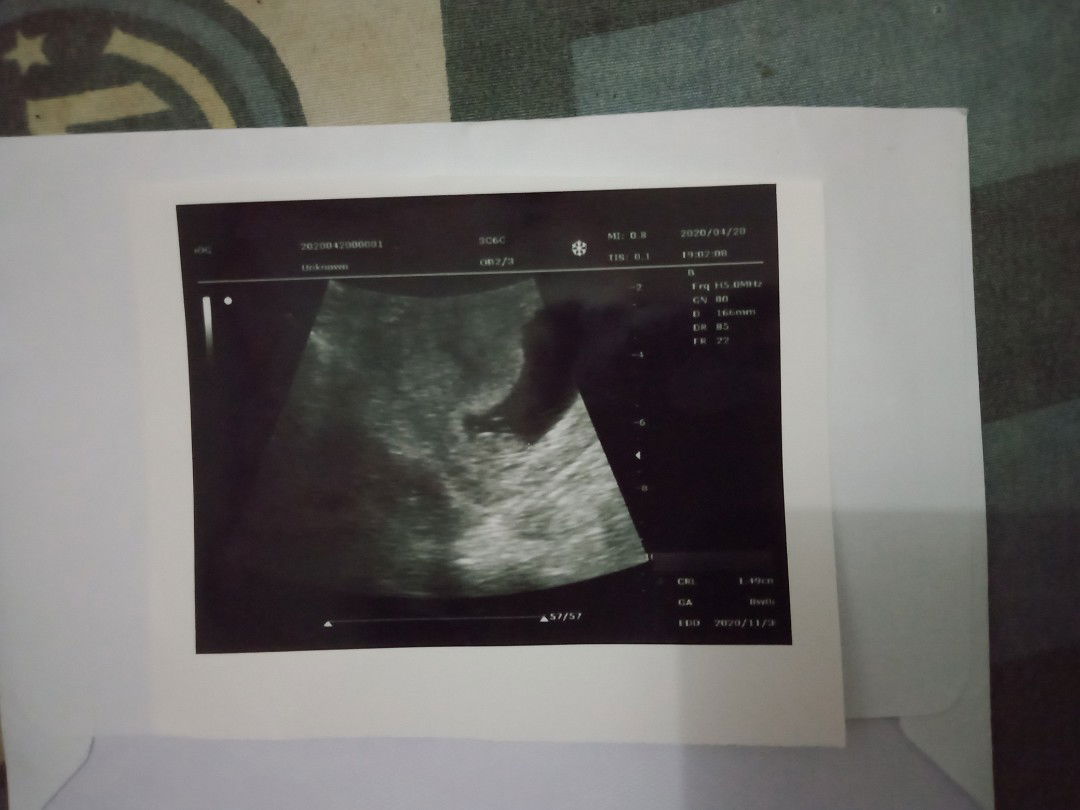

hasil usg

Apakah janin berkembang baik ?